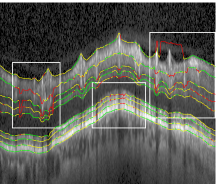

Average boundary-wise results are summarized in Table 2. In general, boundaries 1 and 6 to 9 turned out to be easier to segment than boundaries 2 to 5. For boundary 1 this stems from easily detectable textures, whereas boundaries 6-9 with their regular shape profit disproportionately from regularization by the shape prior. Boundaries 2-5 on the other hand pose a harder challenge with their high variability of texture and shape. The upper row in Fig. 9 shows an example close to the average segmentation performance with Eunsgn=2.97μmsubscript𝐸unsgn2.97𝜇𝑚E_{\mathrm{unsgn}}=2.97\,\mu m.

Refer to caption

(a)

(b)

(c)

(d)

Figure 9: Top: Segmentation (Eunsgn=2.97μmsubscript𝐸unsgn2.97𝜇𝑚E_{\mathrm{unsgn}}=2.97\,\mu m) of a non-pathological circular scan. Bottom: Segmentation (Eunsgn=5.09μmsubscript𝐸unsgn5.09𝜇𝑚E_{\mathrm{unsgn}}=5.09\,\mu m) of an advanced glaucomatous scan.

For the pathological scans segmentation performance was comparable to the healthy scans, but decreased with the progression of the disease. This happened for two reasons: Since glaucoma is known to cause a thinning of the nerve fiber layer (NFL) Schuman et al. (1995); Bowd et al. (2001), the shape prior trained on healthy scans may encounter difficulties adapting to very abnormal glaucomatous shapes. Furthermore, we observed a reduced scan quality for glaucomatous scans, also reported by others Ishikawa et al. (2005); Stein et al. (2006); Mayer et al. (2010), which in turn reduced the quality of the data terms. For advanced primary open-angle glaucoma, the NFL can even vanish at some locations. The appearance model for this layer, trained on healthy data, is not able to detect these extreme anomalies, which resulted in a comparatively low performance for some scans. We discuss possible modifications to overcome this problem in Section 7.

The bottom panels in Fig. 9 show an example of a PGA-type scan and its segmentation. The scan exhibits the discussed reduced scan quality. Furthermore, the segmentation proves that the shape model can generalize well to pathological shapes as well as scan artifacts.